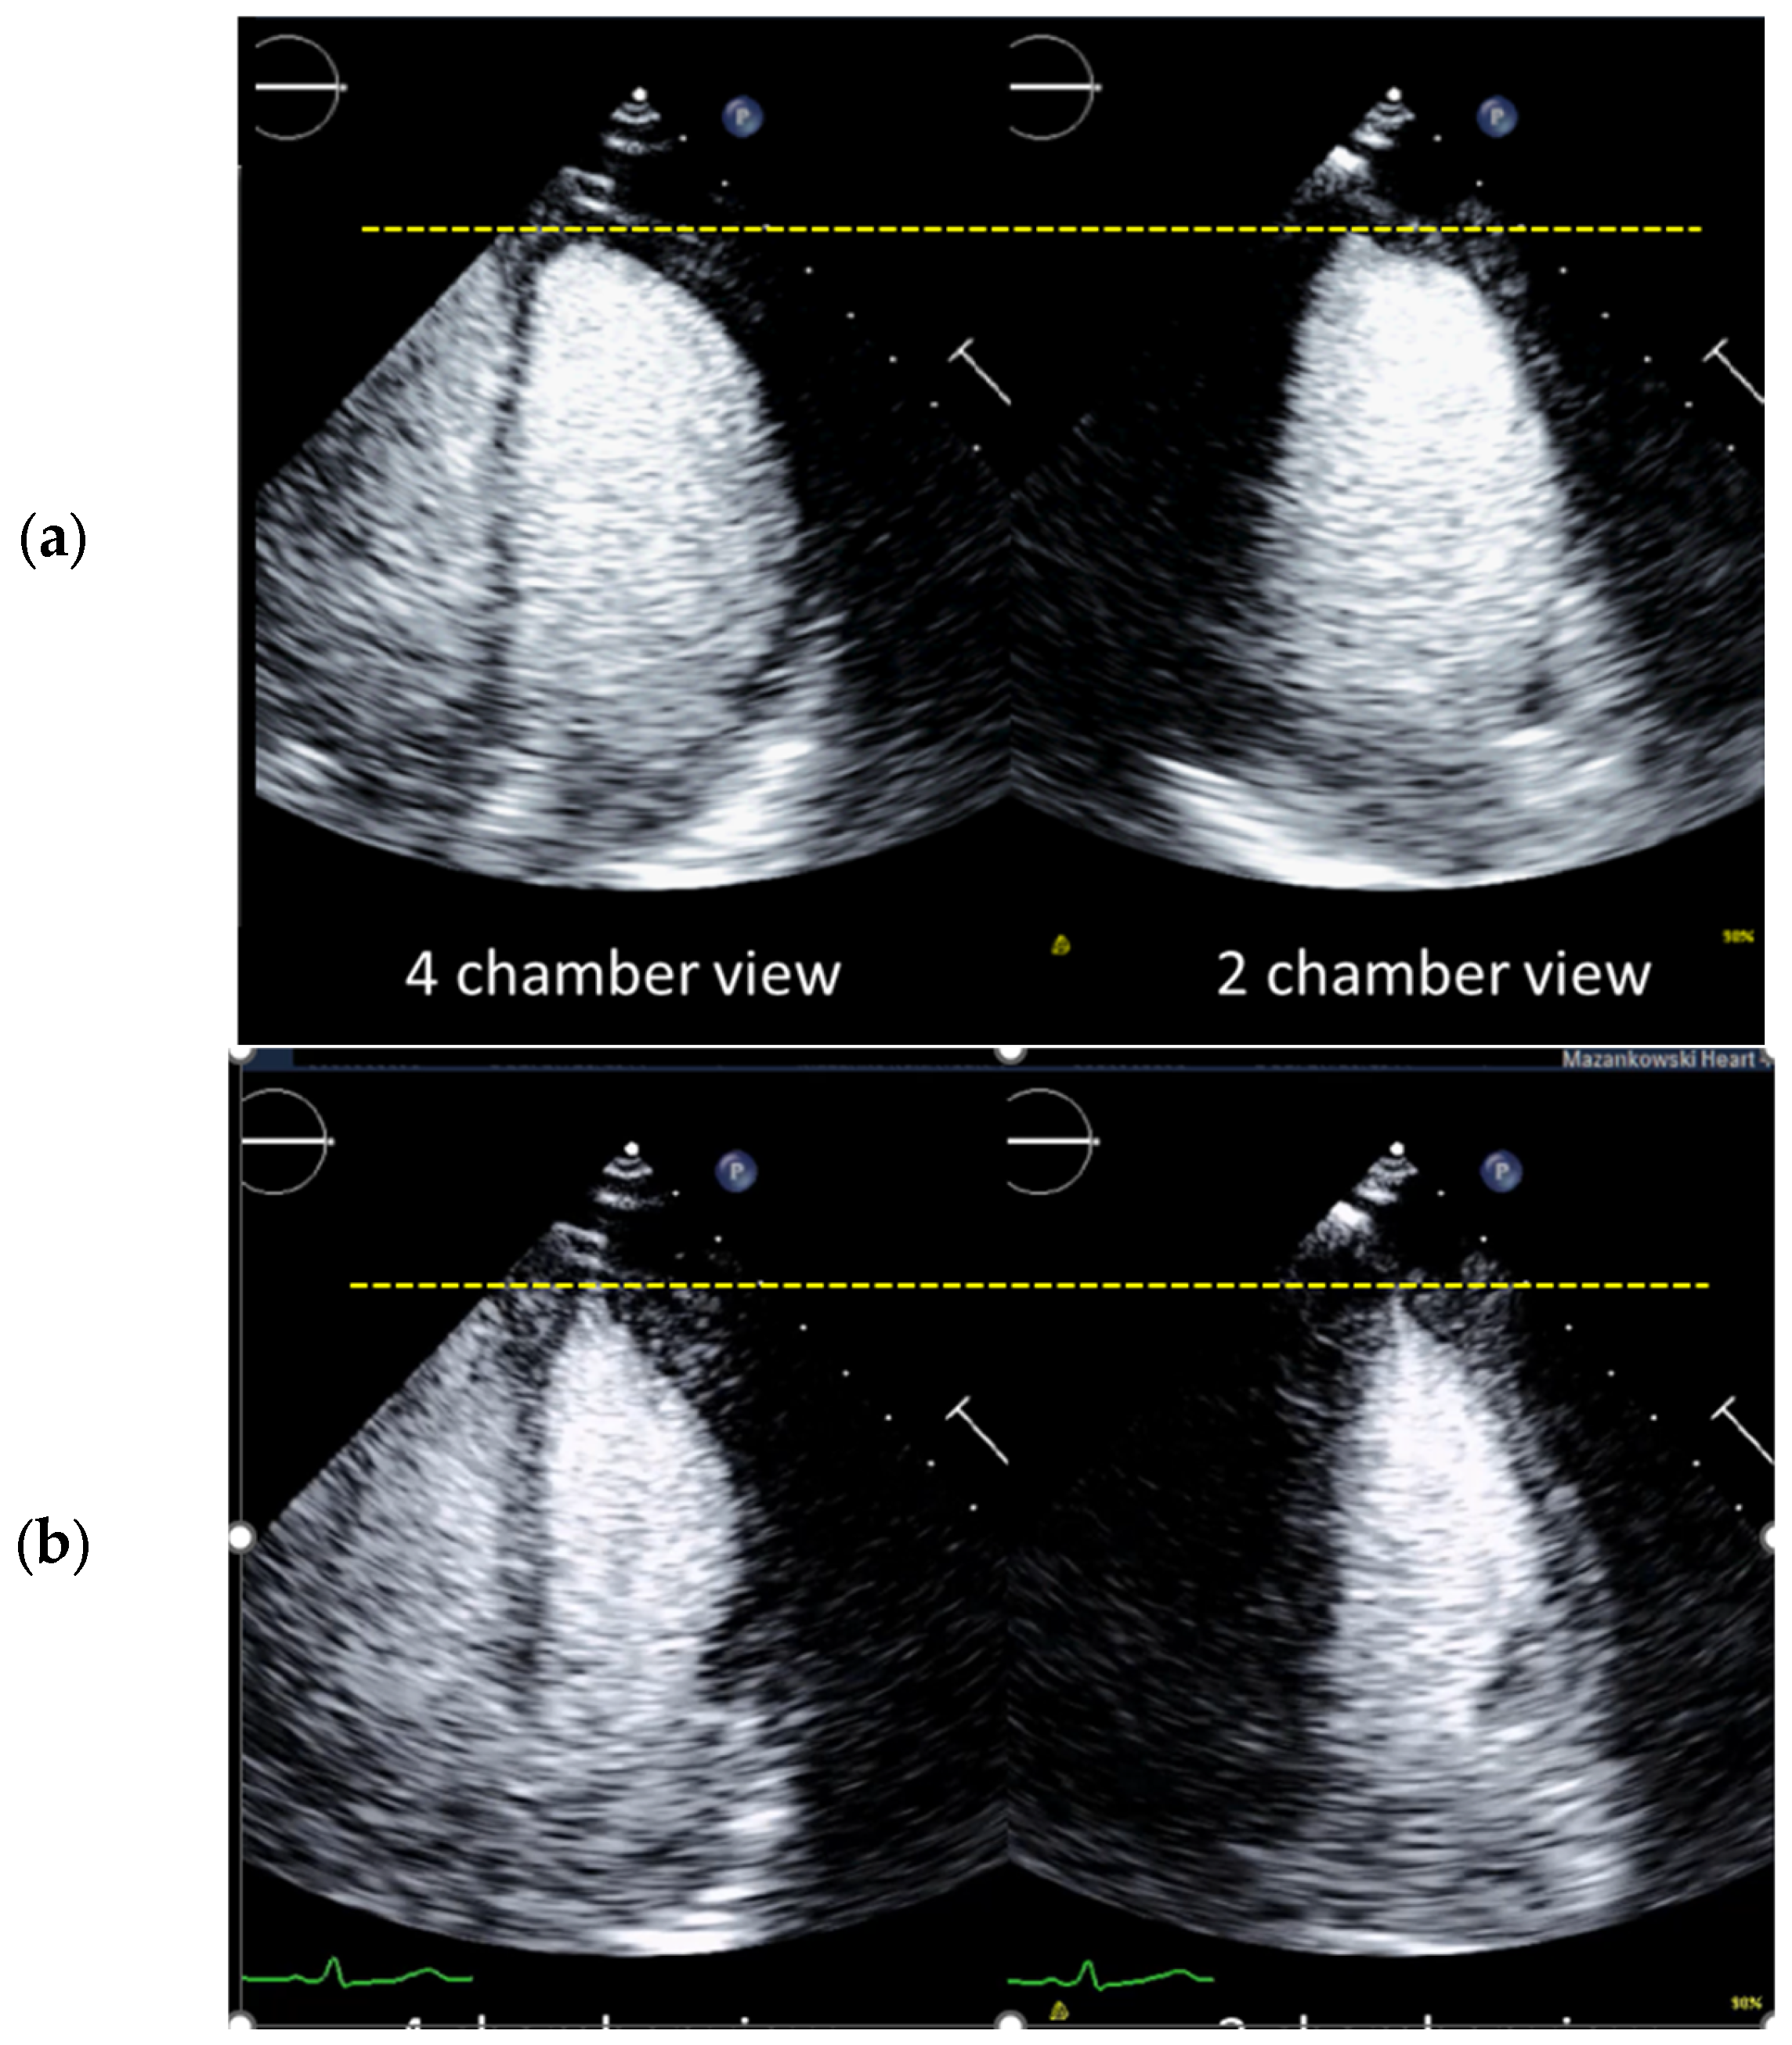

4.4. How to Avoid Foreshortened Imaging Planes

Selection of Foreshortened Loops

| 6 | Check the LV length (distance between the middle of the line connecting the mitral ring and the apex) | When the difference in diastolic LV length between 4- and 2-chamber views is <0.5 cm, no major foreshortening can be assumed When the difference is >5 mm, the recording of the view with the shorter LV length is probably not optimal. The other recordings of this view should be reviewed to find the one with the longest LV [59]. |